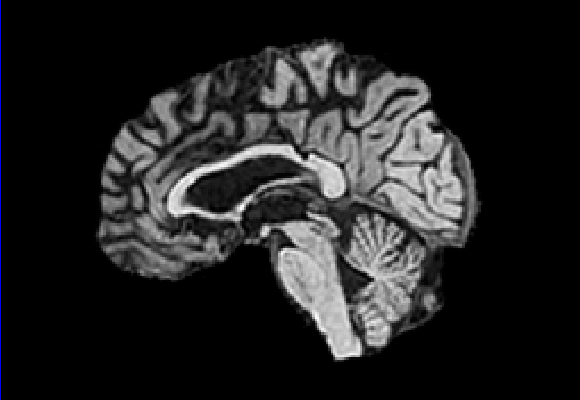

Exp. 2: Fetal brain data is used to test the robustness of our approach under real conditions. Fetuses younger than 30 weeks very often move a lot during examination. Fast MRI sequences allow artifact free acquisition of individual slices but motion between slices corrupts consistent 3D information. Fig. 3 shows that our method is able to accurately predict Ti^^subscript𝑇𝑖\hat{T_{i}} also under these conditions. For this experiment we use ωisubscript𝜔𝑖{\omega_{i}} from three orthogonally overlapping stacks of ssFSE slices covering the fetal brain with approximately 20-30 slices each. We are ignoring the stack transformations relative to the scanner and treat each ωisubscript𝜔𝑖{\omega_{i}} individually. For ΩtrainsubscriptΩ𝑡𝑟𝑎𝑖𝑛\Omega_{train}, 28 clinically approved motion compensated brain reconstructions are resampled into a 150×150×150150150150150\times 150\times 150 volume with 1mm×1mm×1mm1𝑚𝑚1𝑚𝑚1𝑚𝑚1mm\times 1mm\times 1mm spacing. A density of 500 unique sampling normals has been chosen via the Fibonacci sphere sampling method with 25 sampling planes evenly spaced between -25 to +25 on the Z-axis. This gives a plane spacing of 2mm, sampling only the middle portion of the fetal brain. Training took approximately 10hrs for 30 epochs. Prediction, i.e., the forward pass through the network, takes approx. 12 ms/slice.

Figure 3: Comparison of a single slice from a heavily motion corrupted stack of ssFSE T2 weighted fetal brain MRI (a); axial multi planar reconstruction of one sagittal input stack (b); a slice at approximately the same position through a randomly selected training volume (c); failed reconstruction attempt using standard SVR based on three orthogonal stacks of 2D slices (d) (the fetus moved heavily between the acquisition of the individual stacks); reconstruction based on SVRNet Ti^^subscript𝑇𝑖\hat{T_{i}} regression (e); SVR initialised with SVRNet transformations after eight iterations of SVR (f). Note that (e) and (f) are reconstructed directly in canonical atlas co-ordinates.